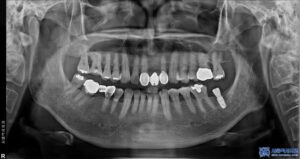

그래서 임플란트 상담을 통해

치료 계획을 세운 후,

무절개 방식의 임플란트 식립을

우선적으로 진행하기로 하였습니다.

환자분은 좌측 아래쪽 어금니가 없는 상태였고,

오랫동안 방치되어 치조골(잇몸뼈)의

변화가 일부 있었습니다.

하지만 다행히도 임플란트를 식립하기에

충분한 골량이 유지되고 있었고,

무절개 방식으로 빠르게

임플란트를 진행할 수 있었습니다.

무절개 방식은 컴퓨터 분석을 통해

미리 임플란트의 식립 위치를 시뮬레이션하여,

수술 시 오차를 줄여주는 방법입니다.

수술 가이드를 활용하여 정확한 위치에

임플란트를 심기 때문에,

잇몸을 절개할 필요 없이 간편하고

안정적인 수술이 가능합니다.